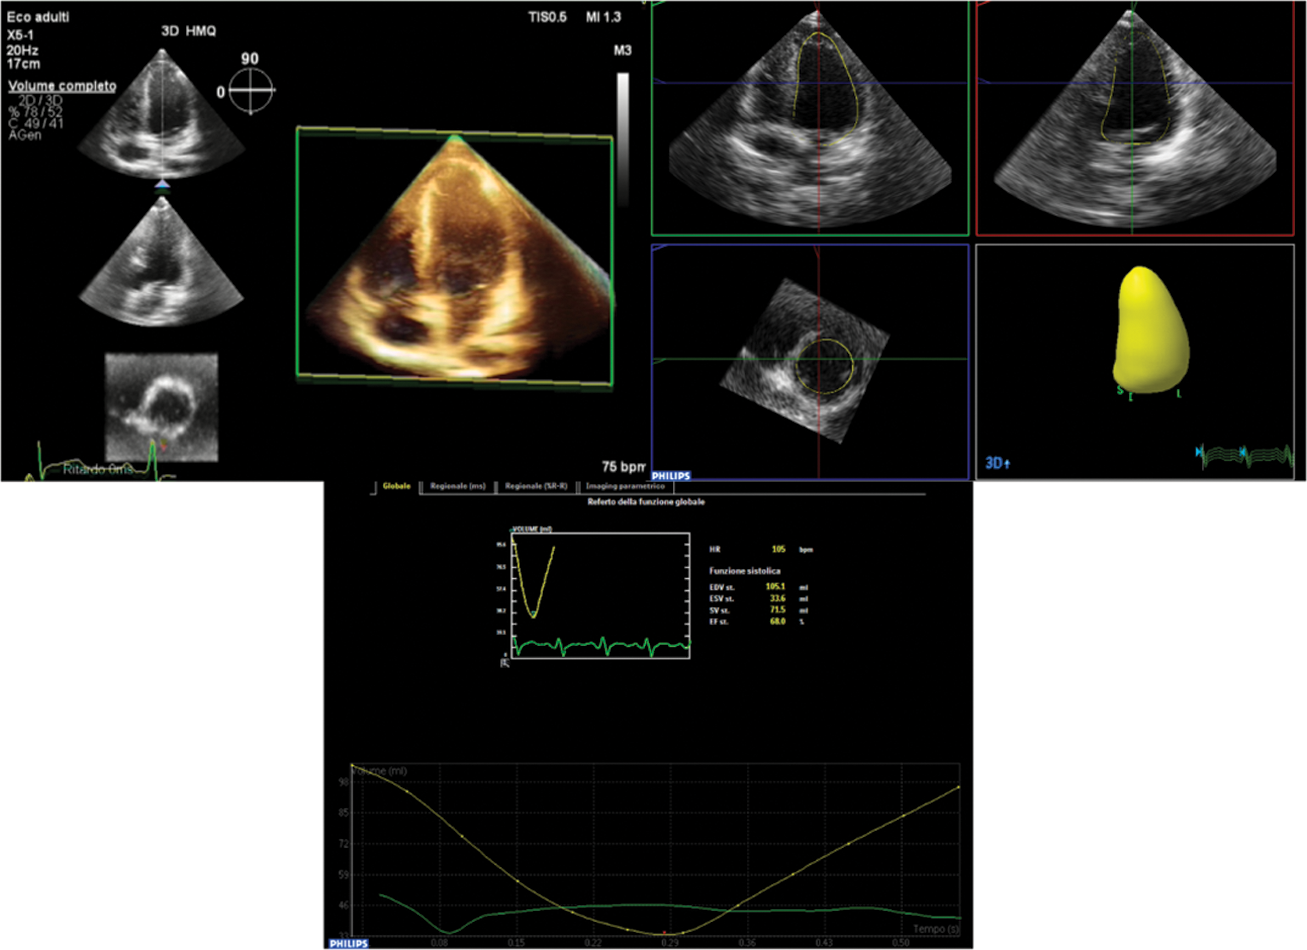

3D examination with full-volume data sets obtained from R-wave triggered two-to four-beat acquisitions. Breath holding was done if the child was able; if the child was unable to hold his or her breath, multiple data sets were acquired, and only those with good quality and without respiratory (“stitch”) artifacts were selected. Images were digitally stored for subsequent off-line analysis on QLAB with Advanced Cardiac 3D Quantification software (3DQA). 3Dend-diastolic and end-systolic LV volumes were measured, with ventricular trabeculae and papillary muscles included in the LV cavity, and end systole was defined as the frame before mitral valve opening. Tracing consisted of setting five points (septal, lateral, anterior and inferior mitral annulus and the apex) followed by semi-automated computation with manual correction of the endocardial contour (Fig. 1).

Figure 1: Measurement of Left Ventricle volumes on the basis of semiautomated identification of endocardial surface by 3DE